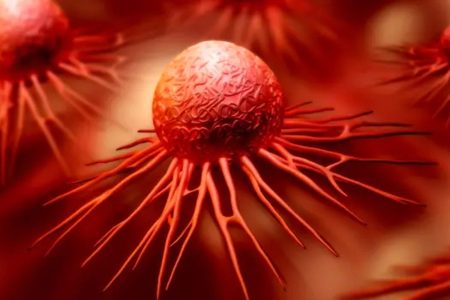

- Zdravlje ljudi zavisi od zdravlja prirode: Zašto je očuvanje okoline ključno za budućnost